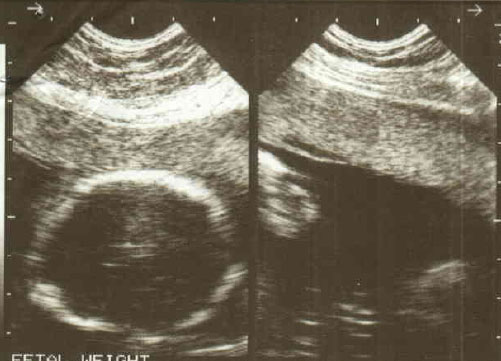

I am expecting a baby first time, below is my ultrasound images.

Please predict the gender of my baby. The ultra sound was done at 18th week.